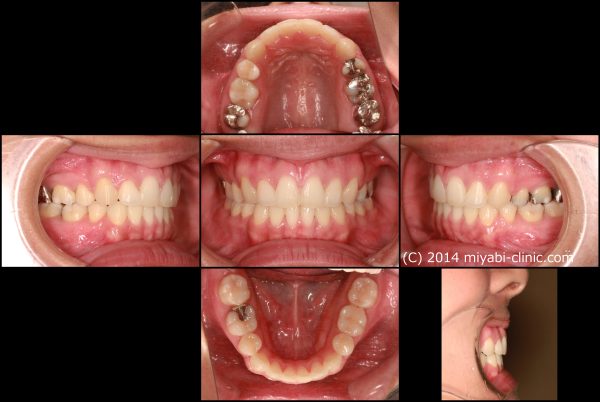

「 出っ歯、口もとを 治してほしい」 22歳 女性 治療期間22か月(上下顎前突症)

22歳の 女性です

「出っ歯、口もとを 治してほしい」との事で来院されました。

前歯が 出ています。 典型的な ”出っ歯” の状態です 少し段差もあります

前歯が 強く傾斜して、骨ごと 前に 出ています

上顎前突症(いわゆる 出っ歯)です

真横から 見るとよくわかりますね